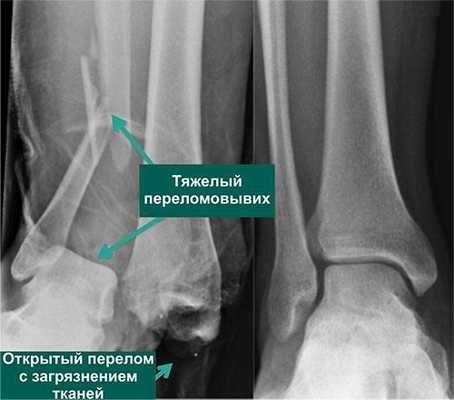

По статистике, 54% переломов и переломо-вывихов голеностопного сустава случаются в молодом возрасте, когда человеку важно сохранять трудоспособность. Эти травмы относятся к тяжелым повреждениям опорно-двигательного аппарата. Даже при качественном лечении они приводят к инвалидности в 3-12% случаев. Поэтому восстановление функций голеностопного сустава требует тщательного подхода, индивидуального для каждого пациента.

Как восстановить функции голеностопа после травмы

- Открытая репозиция с фиксацией погружными конструкциями. Таким путем лечат все открытые и часть закрытых переломов. В некоторых случаях после операции сустав дополнительно фиксируют гипсом.

- Хирургическое лечение. Проводится при застарелых повреждениях связок, посттравматическом остеопорозе, тяжелых переломах и переломо-вывихах. Позволяет восстановить функции голеностопа даже тогда, когда другими путями сделать это невозможно.